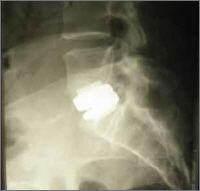

Bei starken Bandscheibenschäden, kann das Einsetzen einer künstlichen Bandscheibe Abhilfe schaffen. In folgenden Fällen rate ich zu einer Operation: